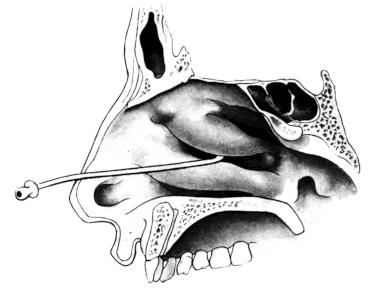

| 345. | Catheterizing the Sphenoidal Sinus | 654 |